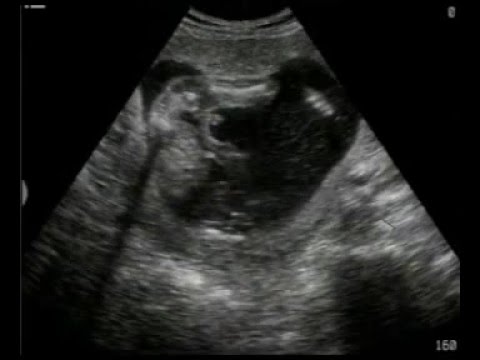

2D Scanning video

uge 30+2

MinGraviditet Redaktion

-

april 29, 2016

0

Min Bassepige får målt maveomfang, lårbensknogle og hovedeomfanget